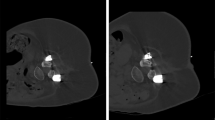

There were no statistically significant differences between patients for SD versus LD scans regarding age, body diameter, or number of sequential scans needed during performance of the intervention (Table 3). Furthermore, no major periprocedural complications (e.g., bleeding) were reported for any of the biopsies performed either with the SD or LD protocol. Figures 4 and 5 depict exemplary patient cases.

Exemplary patient cases for intervertebral disc biopsies using scanning with standard dose (SD; A, B) and scanning with low dose (LD; C, D). The upper row shows a L2/3 intervertebral disc biopsy in a 66-year-old woman (A) and a L5/S1 intervertebral disc biopsy in a 58-year-old woman with artifacts due to spinal instrumentation (B). The second row shows a L5/S1 intervertebral disc biopsy in a 48-year-old male patient (C) and a L4/5 intervertebral disc biopsy in an 80-year-old man with artifacts due to spinal instrumentation (D). All patients underwent intervertebral disc biopsy due to suspected spondylodiscitis.